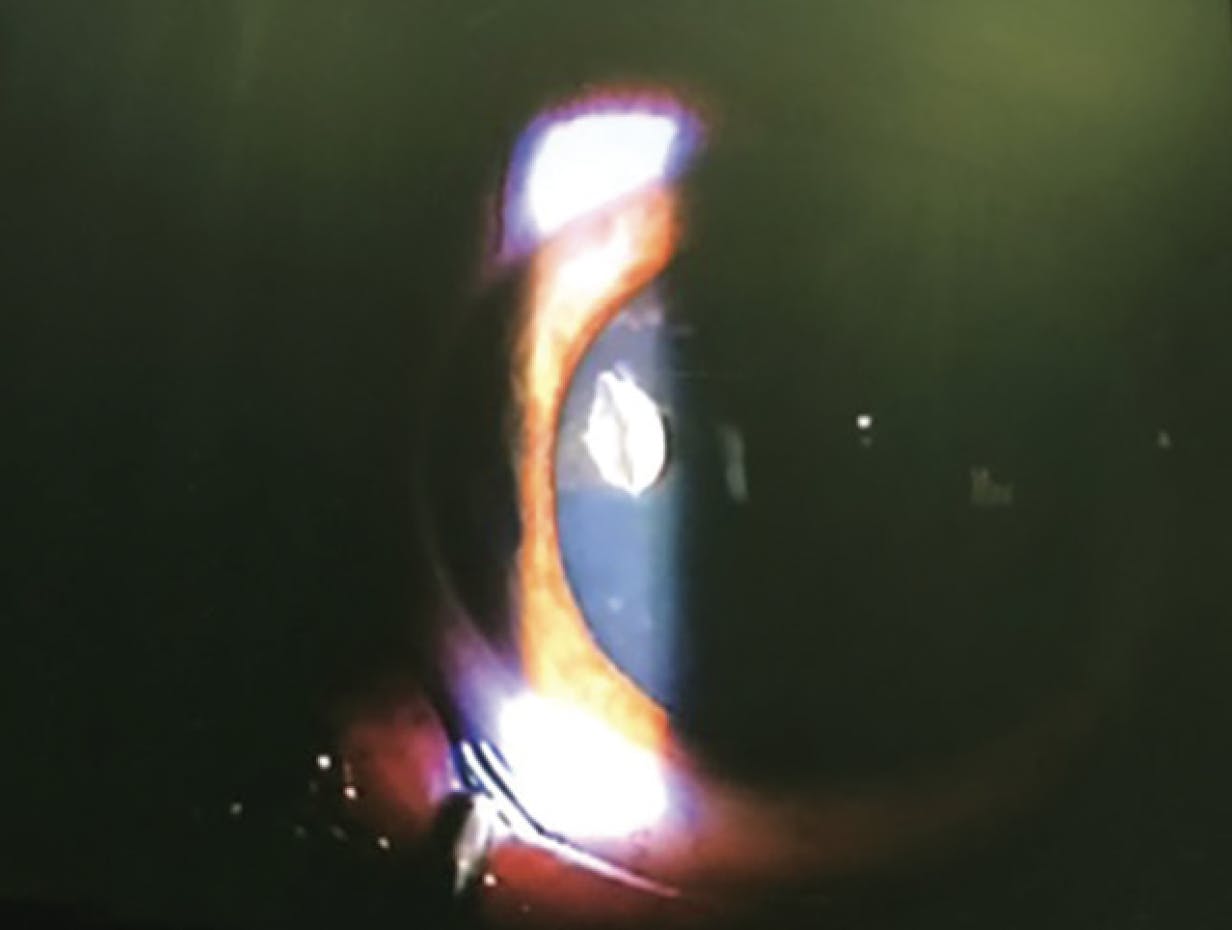

If an IOFB is suspected, a detailed examination of the anterior and posterior segments under mydriasis is required (Figure 1). If visualization is obstructed by opaque media, or an IOFB is suspected in the area of the ciliary body and iris root, further diagnostics (such as B-scan ultrasonography or CT scan) are necessary to locate and evaluate the IOFB.11,12

<p>Figure 1. A careful examination revealed an IOFB in the anterior segment.</p>

Figure 1. A careful examination revealed an IOFB in the anterior segment.